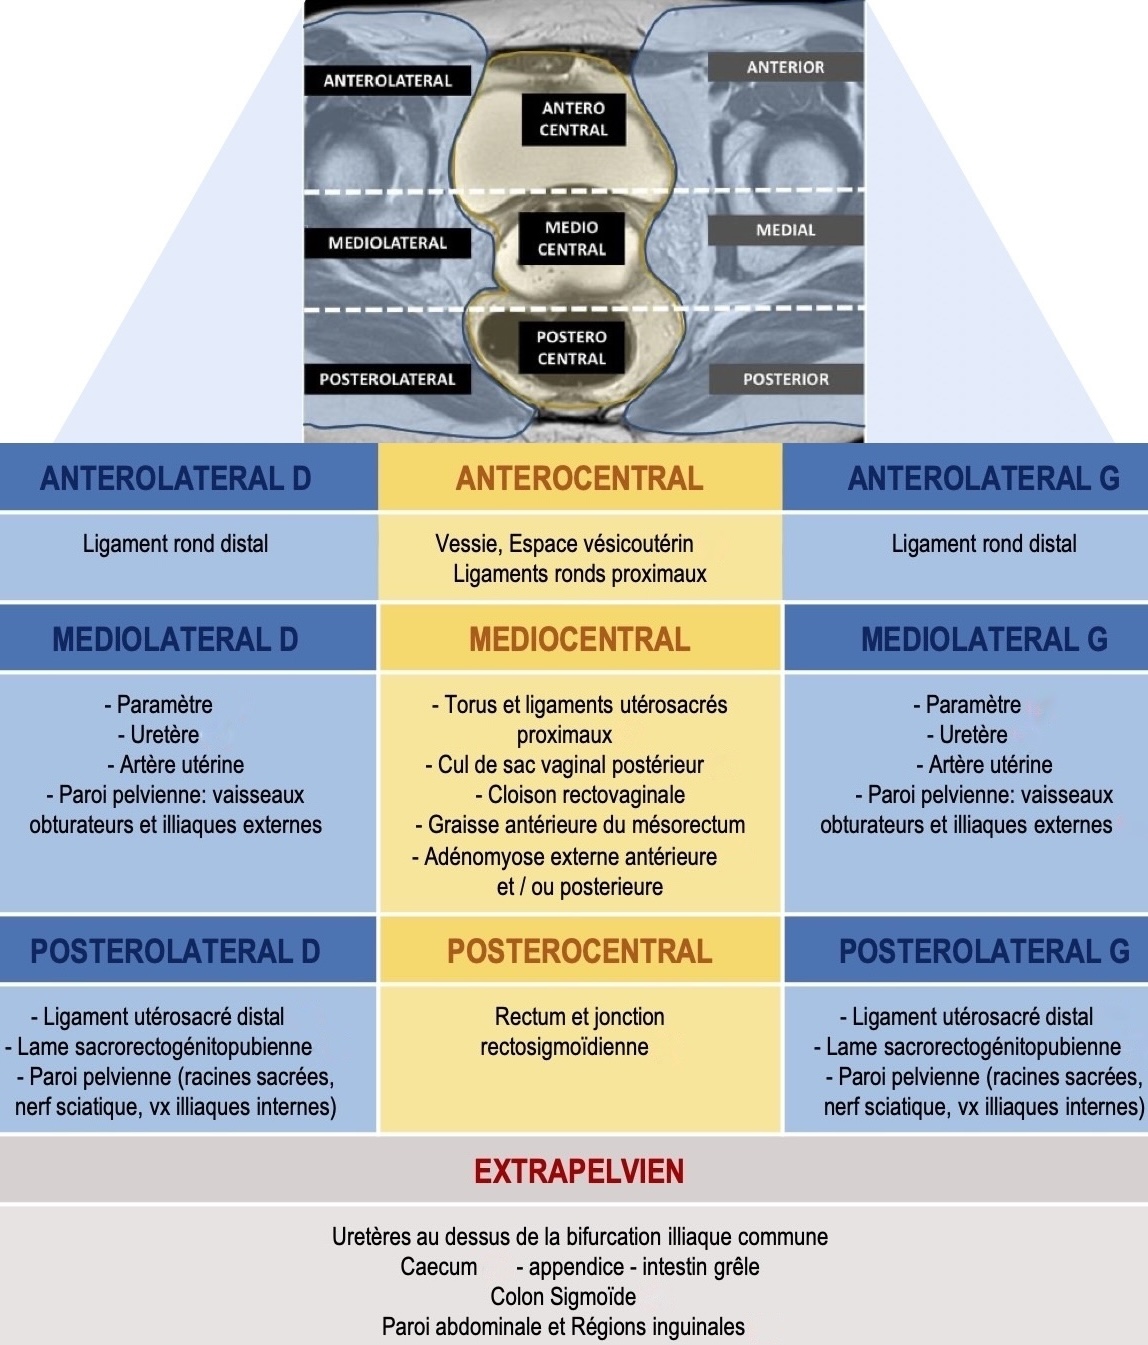

score dPEI (prédit la survenue de complications post-op) = 1 pt/compartiment

+ 1 pt pour vagin, base vessie, dilatation uretère, paroi pelvis

→ extension faible ≤ 2 / modérée 3-4 / majeure ≥ 5

score dPEI (prédit la survenue de complications post-op) = 1 pt/compartiment

+ 1 pt pour vagin, base vessie, dilatation uretère, paroi pelvis

→ extension faible ≤ 2 / modérée 3-4 / majeure ≥ 5

LUS proximal (si critères non remplis « atteinte incertaine »)

épaississement > 3 mm, nodulaire/spiculé dans 2 plans, implant hémorragique

Atteinte digestive

- adhérence

- atteinte pariétale séreuse

- séreuse +/- musculeuse => rectosonographie en cas de décision chirurgicale

- musculeuse : ép. +/- microkystes (largeur ? hauteur ? distance marge anale ? circonf ?)

- endoluminale (préciser épaisseur et degré de sténose si coloscanner)

Atteinte diaphragmatique (T1 FS sag et coro)

- dl thoraciques ou scapulalgies cataméniales, pneumothorax/hémothorax

- le + svt à droite en dh et en arrière de la VCI = hypodense et hyperT1/T2